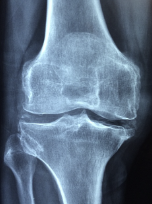

무릎 관절염 증상

무릎 관절염의 증상은 다음과 같습니다.

- 통증: 무릎 관절염의 가장 일반적인 증상은 무릎 주변의 통증입니다. 특히, 오랫동안 앉거나 서 있거나 움직일 때 더 심해집니다.

- 뻣뻣함: 무릎 관절염은 무릎 관절의 뻣뻣함을 유발합니다. 무릎 관절의 움직임이 제한되며, 일어나거나 앉는 것이 어려울 수 있습니다.

- 부종: 무릎 관절염으로 인해 무릎 주변의 부종이 발생할 수 있습니다. 부종은 무릎 관절에 더 많은 압력을 가해 더 많은 통증을 유발합니다.

- 열감: 무릎 관절염은 관절 주위 조직의 염증으로 인해 무릎 주변에서 열감을 느낄 수 있습니다.

- 소리: 무릎 관절염은 무릎 관절에서 윤활제 분비 감소로 인해 뼈가 마찰되어 생기는 부적합한 소리를 유발할 수 있습니다.

무릎 관절염의 증상은 진행되는 정도에 따라 다양합니다. 초기에는 가벼운 통증이 있을 수 있으나, 진행되면서 무릎 관절의 기능 저하와 더 심한 통증이 발생할 수 있습니다. 무릎 관절염이 의심되면, 증상이 심화되기 전에 적극적인 치료와 예방 조치를 취하여 증상의 악화를 방지해야 합니다.